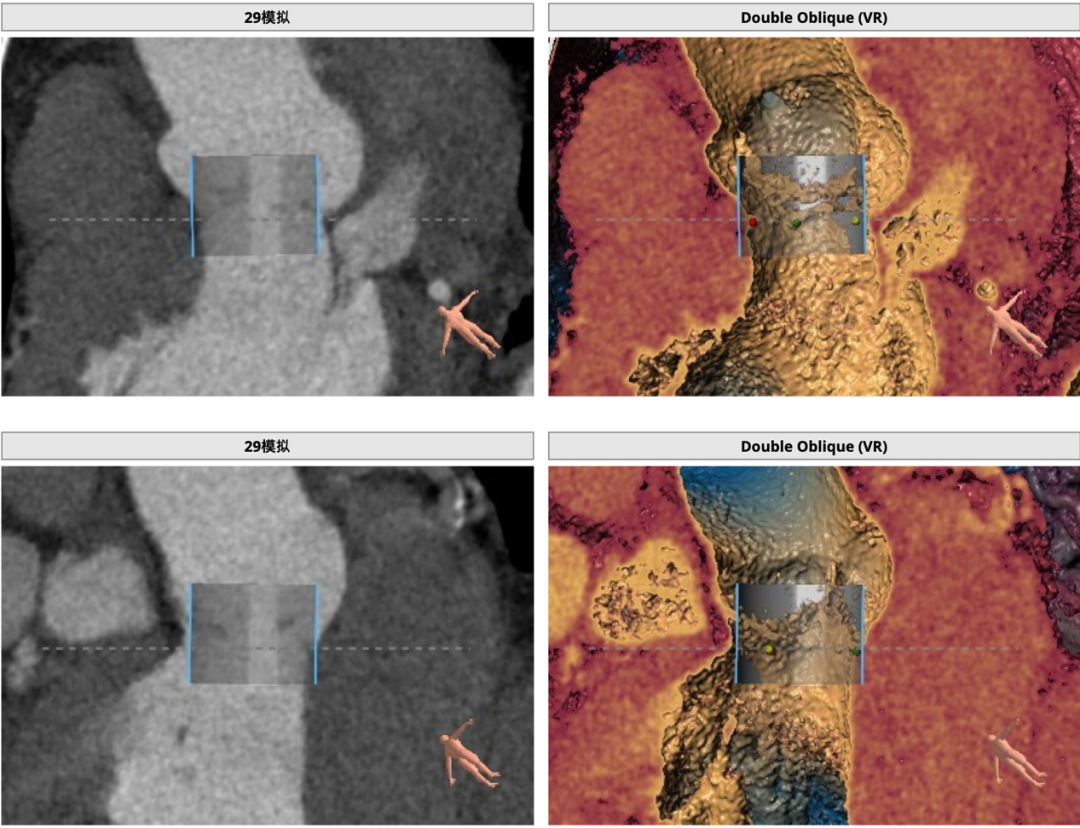

患者主动脉瓣三叶式,瓣叶基本等大,瓣叶增厚,瓣叶未见明显钙化。主动脉瓣环周长折算直径约29.3mm:

主动脉根部径线:

双侧冠脉开口高度可LCA:14.5mm, RCA:22.9mm;右冠轻度钙化,左冠及分支中度钙化:

29mm瓣膜模拟效果: